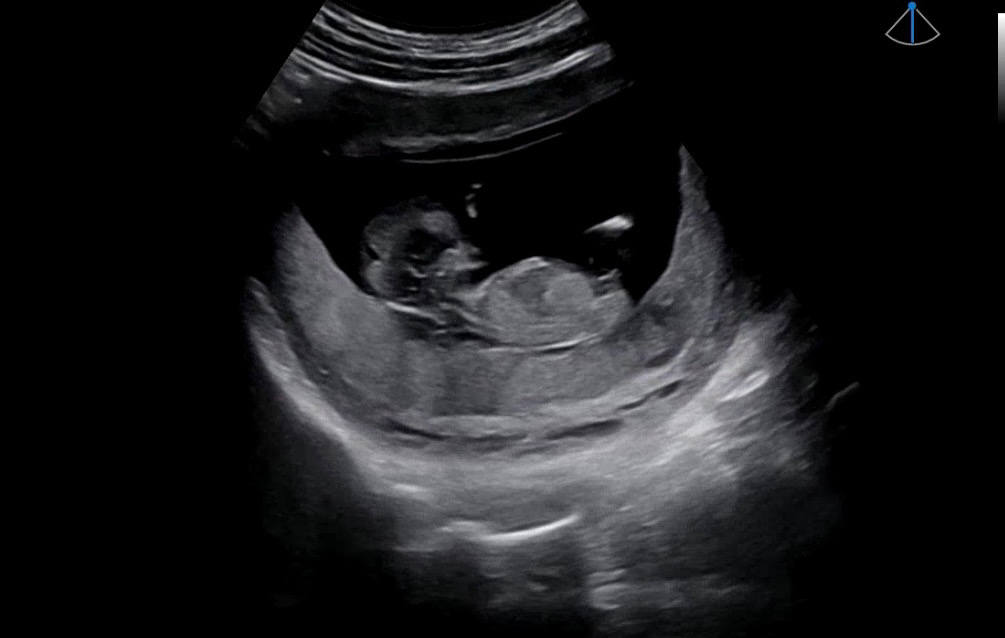

저는 딸에 한표요! 끝에 갈라졋어요

저희 병원은 20주 넘어야 말해준다고 하셔서 ㅠㅠ기다리고 있는데 너무 궁금해서 각도법 보실 수 있는분 부탁드려봐요^_^!!

그쵸 ㅜㅜ 그래서 딸인가 싶었어요!

아들같아요

아들같네요~

아들 같습니다!

아들같아요!

아 진짜요~?끝에 갈라졌는데 아들같으신가요~? 답변 감사합니다💓